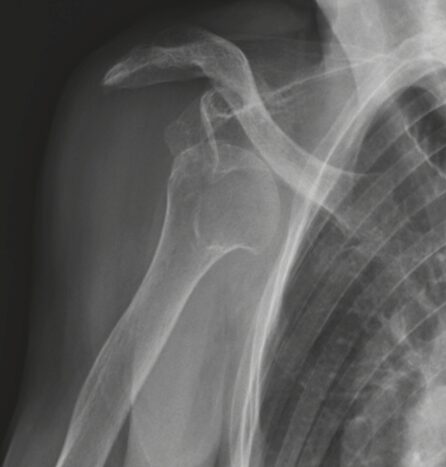

X線(レントゲン)検査

脱臼の方向を確認するほか、骨頭側(ヒル・サックス損傷)や関節窩側(骨性バンカート損傷)に骨の損傷がないかを評価します。反復性肩関節脱臼の診断には必須の検査です。